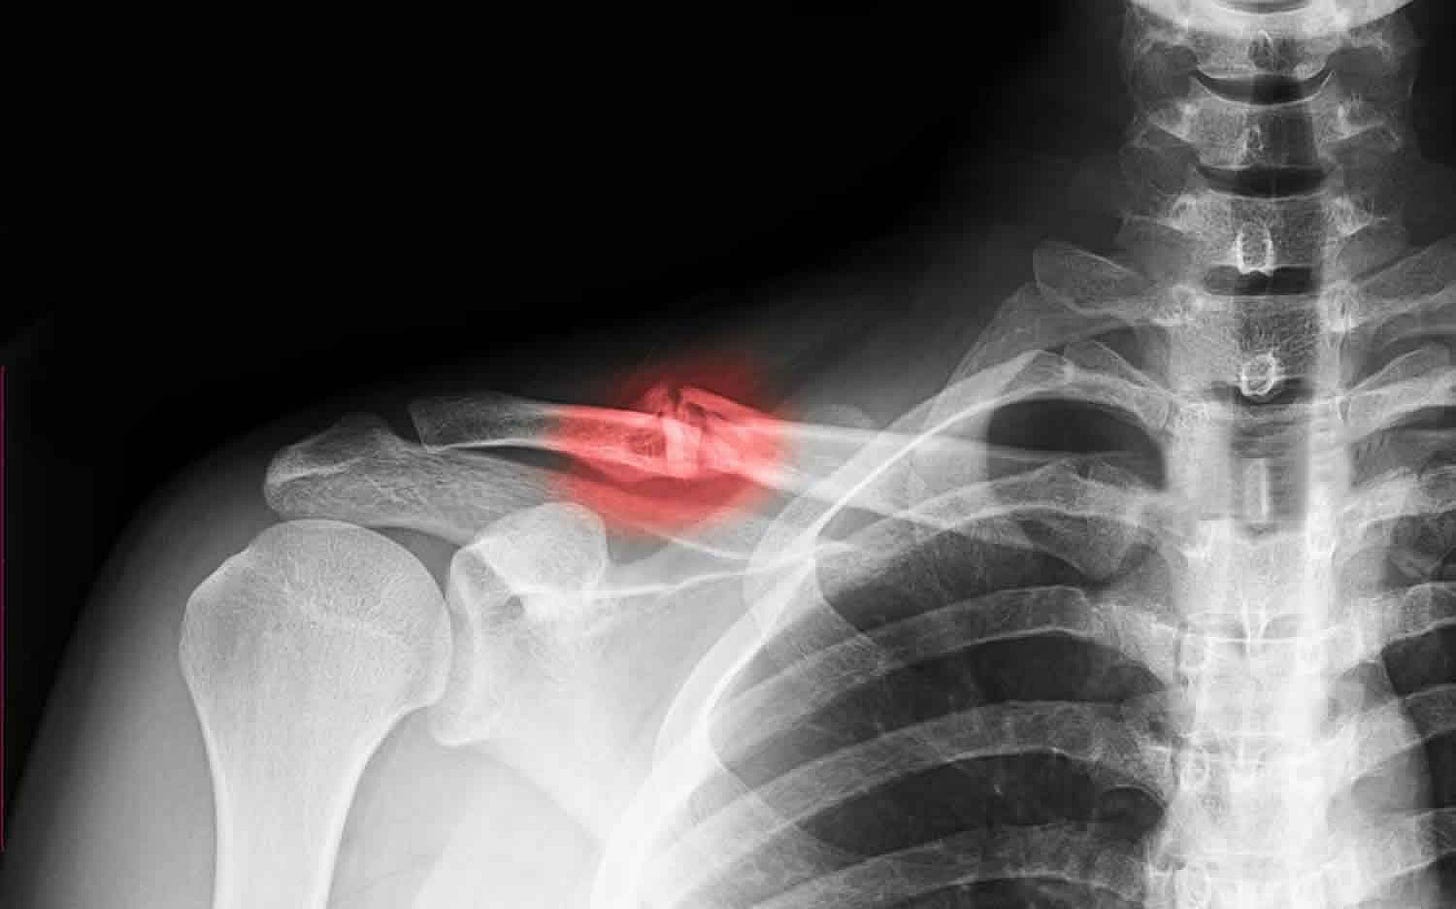

I fractured my clavicle (collarbone) at the end of March falling off a mountain bike. I hadn’t ridden since before Covid but decided to take it back up to improve my stamina for aikido. In 10 years of aikido I’ve never broken anything or really suffered anything more than minor sprains and bruises but third time out on my new bike I did this. The irony was more painful than the injury!